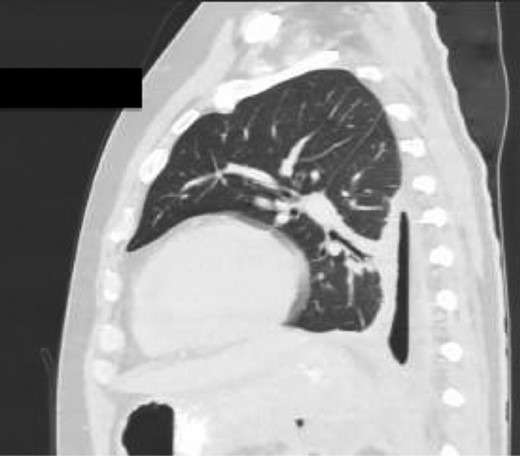

Sagittal view CT Chest revealing large residual space with loss of left lung volume due to the pseudocyst. Image post-transgastric drainage.

Chest X-ray in ICU following drainage showed what was thought to be Pneumomediastinum (Figs 1 and 2), and given this concern he was referred to the Cardiothoracic service. Subsequent CT suggested a large loculated hydro-pneumothorax, which in retrospect represented the drained Pseudocyst communicating through the diaphragm (Figs 3 and 4).